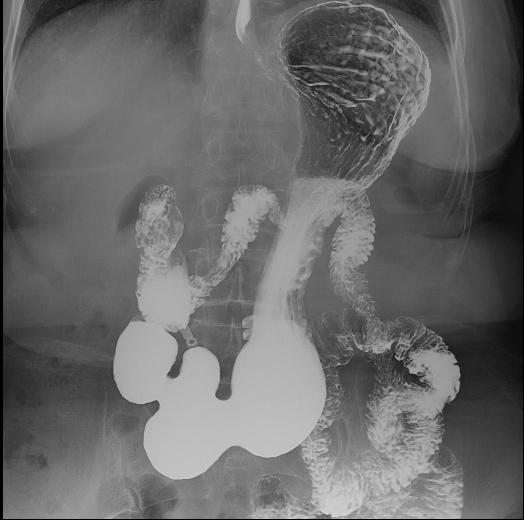

食道造影

胃肠造影